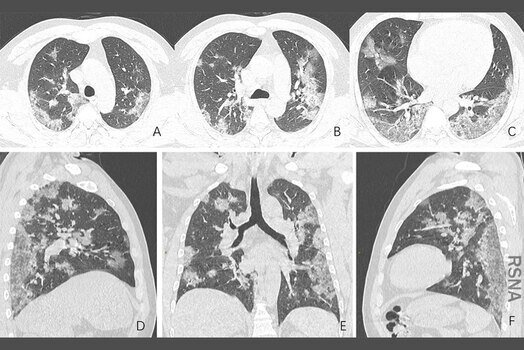

Когда врачи делают снимки их легких-либо с помощью КТ-сканера, либо рентгеновского аппарата-они также выглядят довольно здоровыми. Легкие могут иметь несколько областей помутнения, указывающих на пятна повреждения от их инфекции, но большая часть легких черная, указывающая на то, что она заполнена воздухом.

По словам Гаттинони, около 30% пациентов COVID-19, которые приходят в больницу, имеют затуманеные легкие при сканировании изображений, и они окоченели и воспалены, показывая, что они не работают хорошо. У пациентов также есть низкий уровень кислорода в их крови, и они изо всех сил пытаются дышать. Они выглядят как пациенты с тяжелой пневмонией, вызванной вирусом.